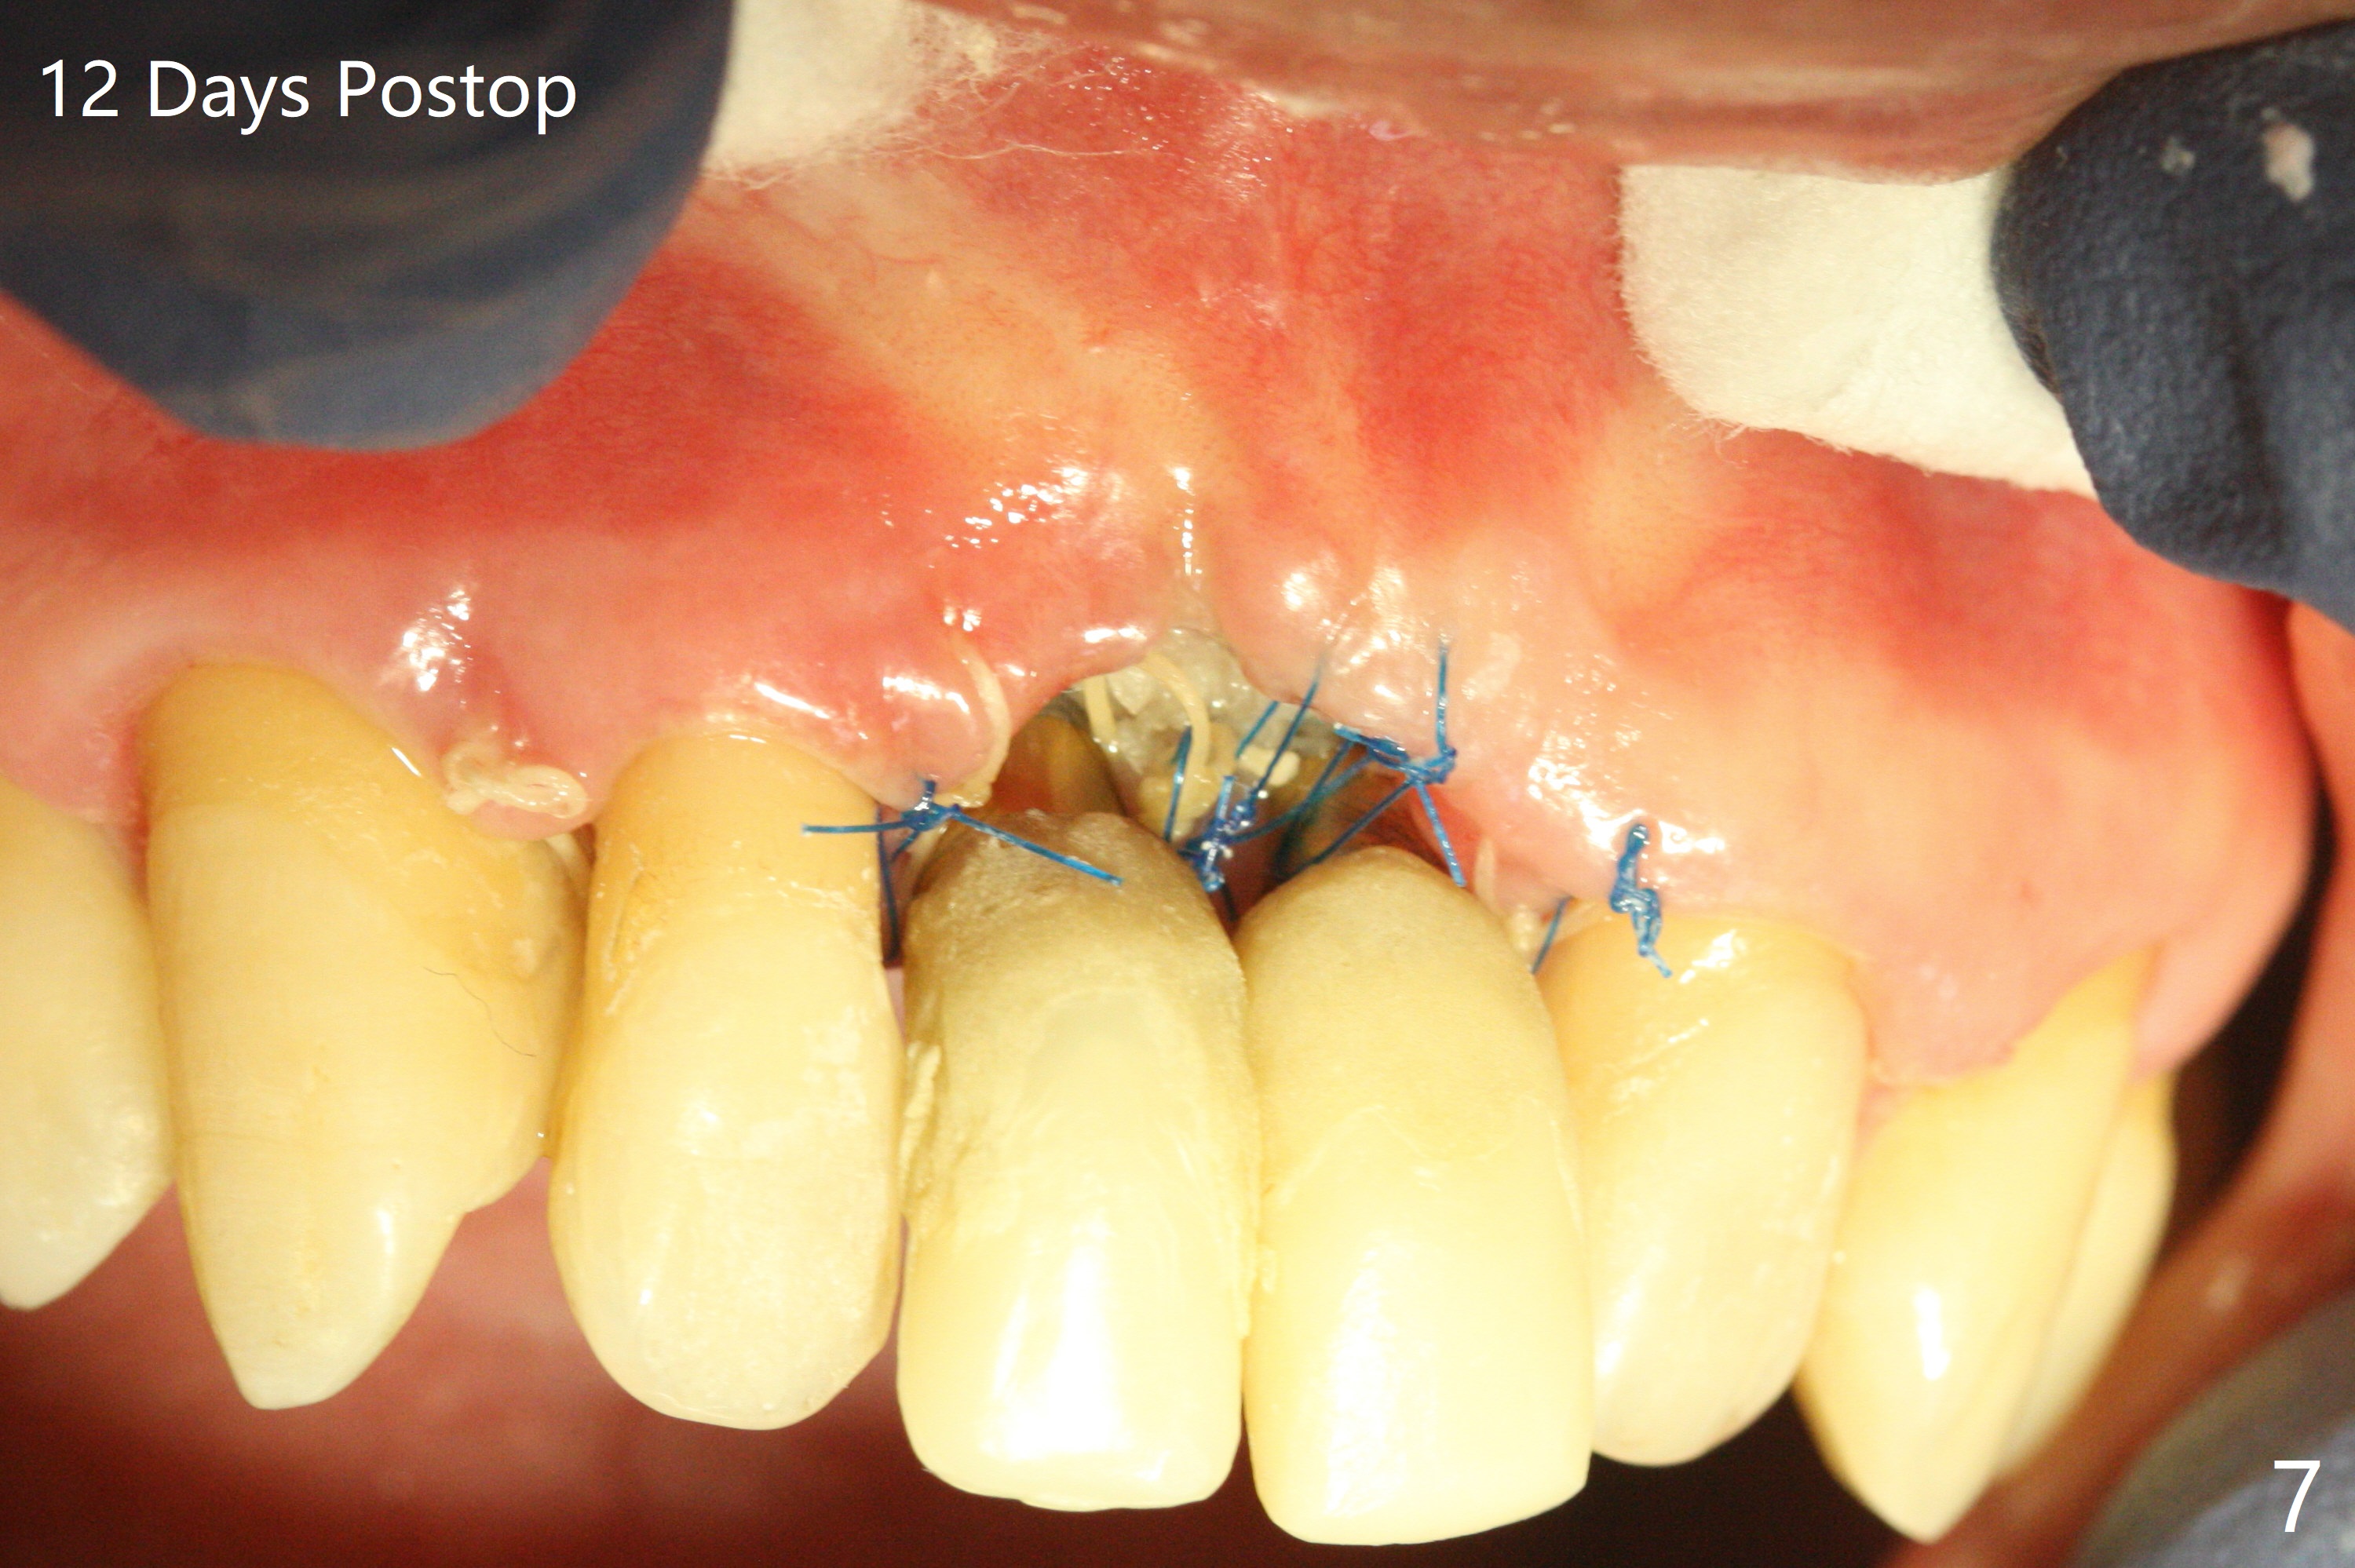

The gingiva remains recessive at #8 and 9 six months post immediate implant placement with bone graft (Fig.1). The buccal plate at #8 is particularly concave before (Fig.2 *) and after (Fig.3) abutment removal. The bony defect repair is assisted by placing a 4 mm tenting screw between the 2 implants (Fig.4) and placing allograft mixed with PRF (as putty) around the screw (Fig.5 (after replacement of the abutments)). The buccal contour improves because of the tenting screw and the bone graft placement (Fig.6 (as well as PRF and 6-month membranes)). The wound dehisces 12 days postop and immediately before leaving country for months (Fig.7). The sutures are removed, Osteogen plug is inserted (Fig.8) and periodontal dressing is applied (Fig.9). PA is taken to show the tenting screw (Fig.10 T). The latter is exposed 3 months postop (Fig.11,12). It appears that gingival graft is a must (Fig.13). Make a palatal stent, remove the temp with abutments and create a bleeding surface before harvesting a large piece of tissue. Connective tissue graft is done 5 months post bone graft (Fig.14). In fact there is no implant thread exposure. In fact the connective tissue graft does not survive. The abutments are re-prepared for pink porcelain (Fig.15). The bone loss is stable 1 year post cementation in spite of incomplete abutment seating (Fig.16). The soft tissue is nearly normal (Fig.17).